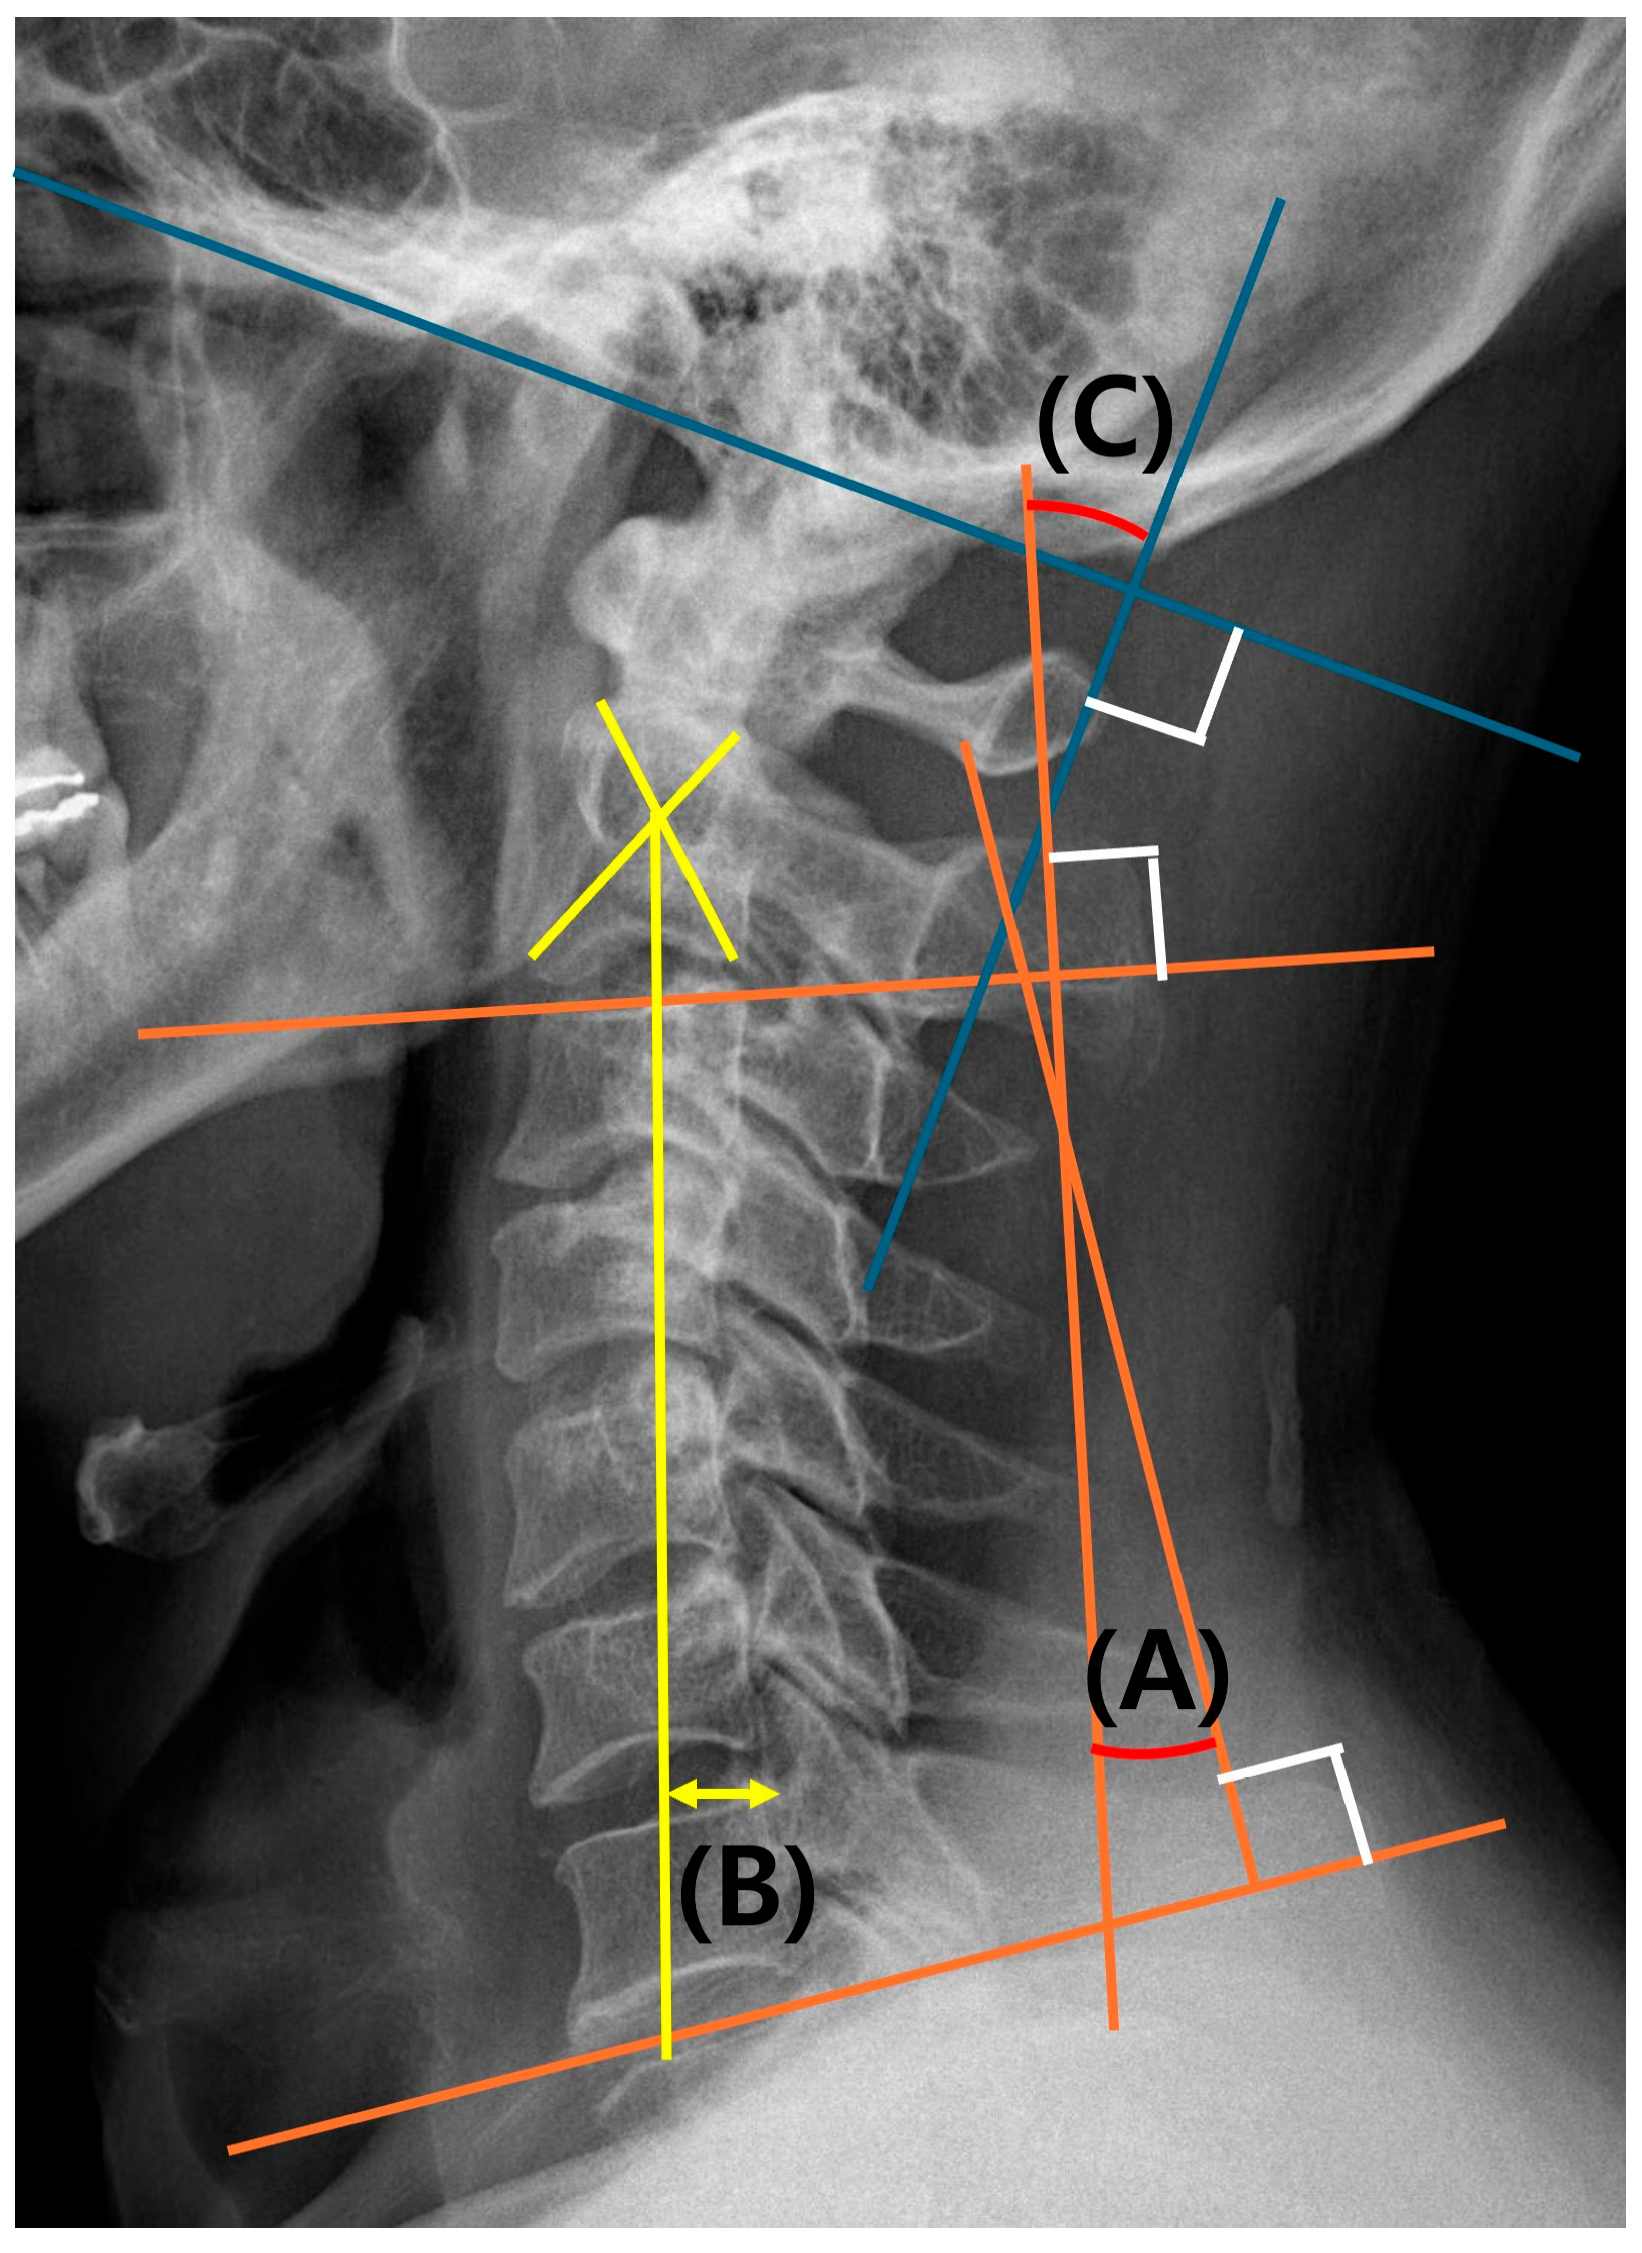

2.3.2. Evaluation of Cervical Alignment